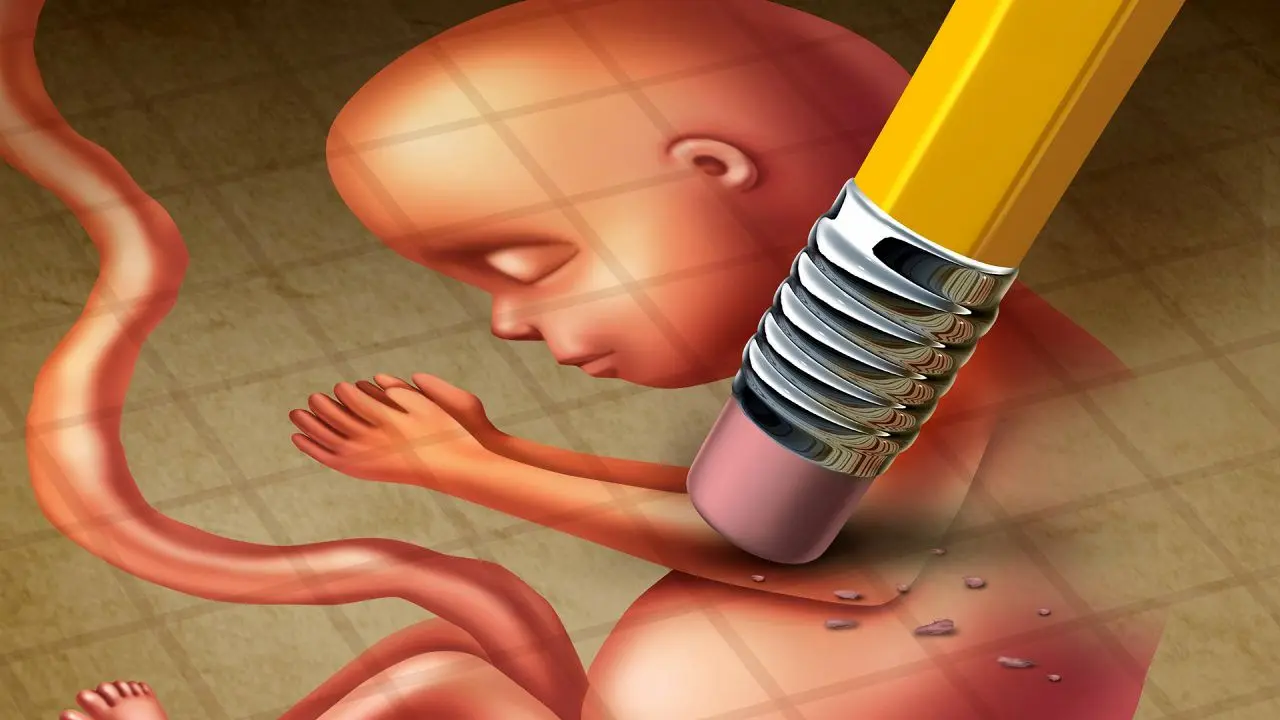

حمله آمریکا و اسرائیل به پژوهشکده لیزر دانشگاه شهید بهشتی/ ۹۰ درصد تجهیزات از بین رفتسقط جنین فقط در شرایطی تحت نظارت پزشکی انجام میشود که پزشک تشخیص دهد نگه داشتن جنین به دلایل مختلف سلامت مادر را تهدید میکند یا با توجه به موارد خاص پزشکی به دنیا آوردن جنین یا وضعیت زنده ماندن آن تحت شرایط خاصی غیرممکن است.

معاونت بهداشت وزارت بهداشت، درمان و آموزش پزشکی با انتشار بیانیهای نسبت به برخی اخبار نادرست و تحریفشده درباره

سقط جنین، بهویژه در خصوص موارد مربوط به سندروم داون، واکنش نشان داد و توضیحاتی جهت تنویر افکار عمومی ارائه کرد.

طی روزهای اخیر مطالبی خلاف واقع به نقل از رئیس مرکز جوانی جمعیت، سلامت خانواده و مدارس در برخی رسانههای داخلی و خارجی منتشر شده که مغایر با

مفاد قانونی و رویکرد رسمی نظام سلامت کشور است.

در بیانیه معاونت بهداشت وزارت بهداشت در این زمینه آمده است: «سقط عمدی جنین، از نظر شرعی و قانونی، ممنوع است؛ مگر در موارد استثنایی که در ماده ۵۶ «قانون حمایت از خانواده و جوانی جمعیت» بهصراحت پیشبینی شده باشد.

بر اساس این ماده قانونی، صدور مجوز سقط جنین تنها در صورت احراز شش شرط ممکن است:

رضایت مادر

وجود حرج (مشقت شدید و غیرقابل تحمل) برای مادر

وجود قطعی ناهنجاریهای جنینی غیرقابل درمان در مواردی که منشأ حرج، بیماری یا نقص جنین باشد

عدم امکان جبران و جایگزینی برای حرج مادر

نبود نشانههای ولوج روح

کمتر بودن سن جنین از چهار ماه

در مورد جنین مبتلا به سندروم داون نیز، امکان سقط تنها در صورت طی مراحل قانونی و احراز شرایط ماده ۵۶ وجود دارد. سه شرط اصلی در این خصوص عبارتند از:

درخواست و رضایت مادر

تشخیص قطعی سندروم داون بر اساس دستورالعملهای وزارت بهداشت

احراز وجود حرج غیرقابل تحمل برای مادر توسط قاضی در کمیسیون قانونی سقط»

معاونت بهداشت در پایان این بیانیه تأکید کرده است که «تمام تصمیمات مرتبط با سقط جنین، با رعایت کامل موازین شرعی، قانونی و مصالح خانواده و جامعه اتخاذ میشود و اخبار منتشرشده اخیر درباره تغییر در این روند، فاقد صحت است.» /تابناک

سقط جنین فقط در شرایطی تحت نظارت پزشکی انجام میشود که پزشک تشخیص دهد نگه داشتن جنین به دلایل مختلف سلامت مادر را تهدید میکند یا با توجه به موارد خاص پزشکی به دنیا آوردن جنین یا وضعیت زنده ماندن آن تحت شرایط خاصی غیرممکن است. در این مقاله، روشهای مختلف سقط جنین، عوارض جسمی و روحی آن، شرایط قانونی در ایران و دیگر کشورها، و همچنین مراقبتهای پس از سقط جنین را بهطور دقیق شرح دادیم. هدف از این توضیحات، فراهم آوردن اطلاعات صحیح و علمی برای زنان و خانوادهها است تا در صورت نیاز به این تصمیم، بتوانند با کمترین خطرات جسمی و روحی ممکن اقدام به سقطط جنین کنند. برای کسب اطلاعات برای سلامت بیشتر خود و عزیزانتان تا انتهای این مقاله با ما همراه باشید.

سقط جنین فرآیند خاتمه دادن به بارداری قبل از رسیدن جنین به سن قابل تولد است. این تصمیم میتواند به دلایل مختلفی اجرا شود، از جمله مشکلات پزشکی که میتواند سلامت مادر یا جنین را به خطر اندازد. این شرایط در اقدام به سقط قانونی در جریان است و در شرایط سقط جنین به صورت غیرقانونی متاسفانه خانمها خسارتهای غیرقابل جبرانی به روح و جسم خود وارد میکنند. هرچند برخی با دلایلی همچون شرایط سخت اقتصادی یا خانوادگی چنین تصمیم ناراحت کنندهای میگیرند، اما بهترین گزینه در این مورد پیشگیری از بارداری به صورت تخصصی و بهداشتی است که در ادامه مقاله به آن خواهیم پرداخت.

سقط جنین به دو روش دارویی و جراحی قابل انجام است. انتخاب هر کدام از این روشها توسط پزشک بستگی به عواملی همچون سن بارداری، وضعیت سلامت مادر و همچنین شرایط پزشکی خاص وی دارد. پزشک متخصص با در نظر گرفتن این عوامل، روش مناسب و مجزایی را برای هر بیمار تجویز میکند. توجه داشته باشید که برای اقدام به سقط جنین، انجام آزمایشات اولیه و مشاوره پزشکی الزامی است تا از وقوع هرگونه عوارض ناخواسته جلوگیری گردد.